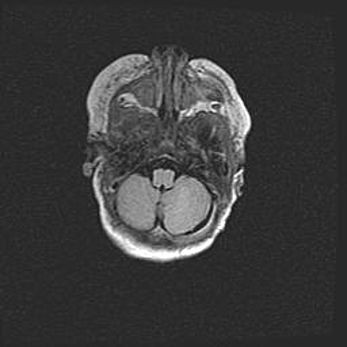

Подострая гематома правой гемисферы мозжечка.

Наружная гидроцефалия.

Возраст: 15 дней

Вес: 3100 г

Пол: женский

Окружность головы: 37 см

Срок гестации: 35-36 недель

При открытой наружной форме гидроцефалии у новорожденных расширяются и переполняются субарахноидные пространства.

Кровоизлияния в мозжечок имеют две клинико-анатомические формы: полушарные гематомы и кровоизлияния в червь.

К появлению этой патологии может привести: повреждения головного мозга, возникающие в результате асфиксии и гипоксии плода при беременности, или травмы во время родов. Редко гематома мозжечка может быть результатом первичной коагулопатии и сосудистой мальформации, диссеминированном внутрисосудистом свертывании, изоиммунной тромбоцитопении.